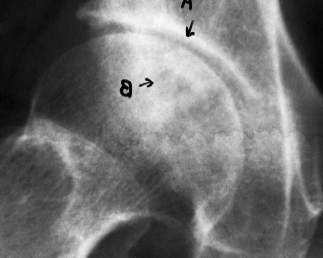

病例1,男,56岁,5年内剧烈疼痛,活动受限。经过16个月的治疗,患者恢复了正常工作。治疗前,股骨头形状模糊,关节间隙不清,密度不均匀,坏死面积占70%(a)。治疗后股骨头表面光滑,密度均匀,骨小梁均匀,关节间隙正常(b)

Case 1, male, 56 years old, had severe pain and limited activity in 5 years. After 16 months of treatment, the patients returned to normal work. Before treatment, the shape of femoral head was vague, the joint space was unclear, the density was uneven, and the necrosis area accounted for 70% (a). After treatment, the surface of femoral head was smooth, the density was even, the bone trabecula was even, and the joint space was normal (b).

病例2女,59岁,类风湿性关节炎伴骨坏死13年,不能下床,进食后可优于轻体力劳动。用药前,双侧关节间隙消失,股骨头密度不均匀(a1,2)。用药后双侧关节间隙出现,股骨头表面光滑,骨密度均匀(b1,2)。

Case 2 female, 59 years old, rheumatoid with osteonecrosis for 13 years, can not get out of bed, can be better than light work after eating.

Before eating, the bilateral joint space disappeared and the density of femoral head was uneven (a1,2). After eating, bilateral joint space appeared, the surface of femoral head was smooth and bone density was even (b1,2).